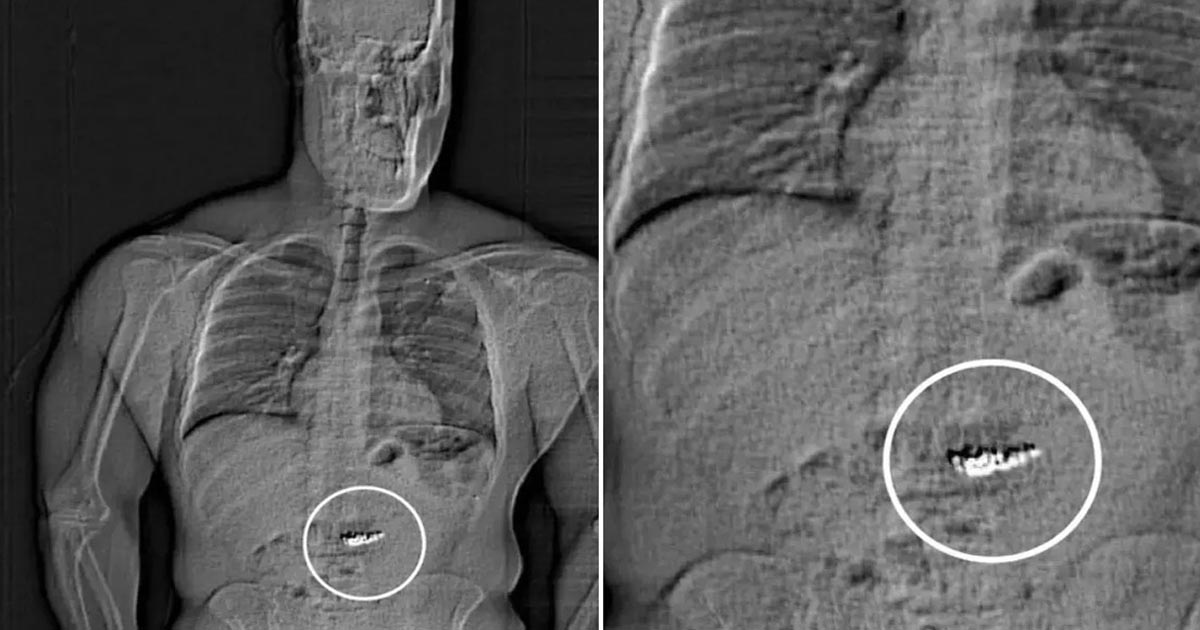

Tras escanear su cuerpo, los detectives encontraron objetos extraños recorriendo su tracto digestivo y determinaron que eran las joyas. Actualmente se enfrenta a cargos de hurto mayor en primer grado y robo con el rostro cubierto. RT